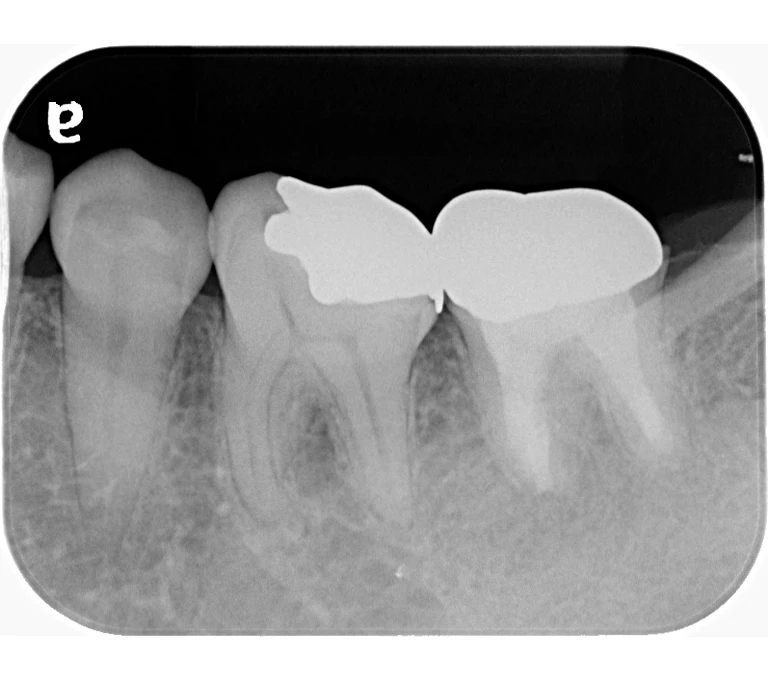

case 1.

治療前

治療後

| 主訴 | 右下歯ぐきの腫れ。 他院で抜歯と言われ、セカンドオピニオン希望でご来院。 |

|---|---|

| 治療期間 | 1か月 |

| 治療費 | 約2万円 |

| 治療内容 | ラバーダム、マイクロスコープ下にて根管治療を施術。歯肉腫脹と疼痛は消失し補綴物を作製し治療終了。治療後のレントゲン写真は2年後のものです。 |

| 治療のリスク | マイクロスコープやCTを使用し、可能な限り精密な根管治療を行っていますが、歯根の形態や病変の大きさ、過去の治療履歴などにより、治癒が得られない場合があります。 また、治療後に再感染や歯根破折が生じることもあり、その場合は再治療や抜歯が必要となることがあります。 治療結果には個人差があり、すべての症例で同様の経過を保証するものではありません。 |